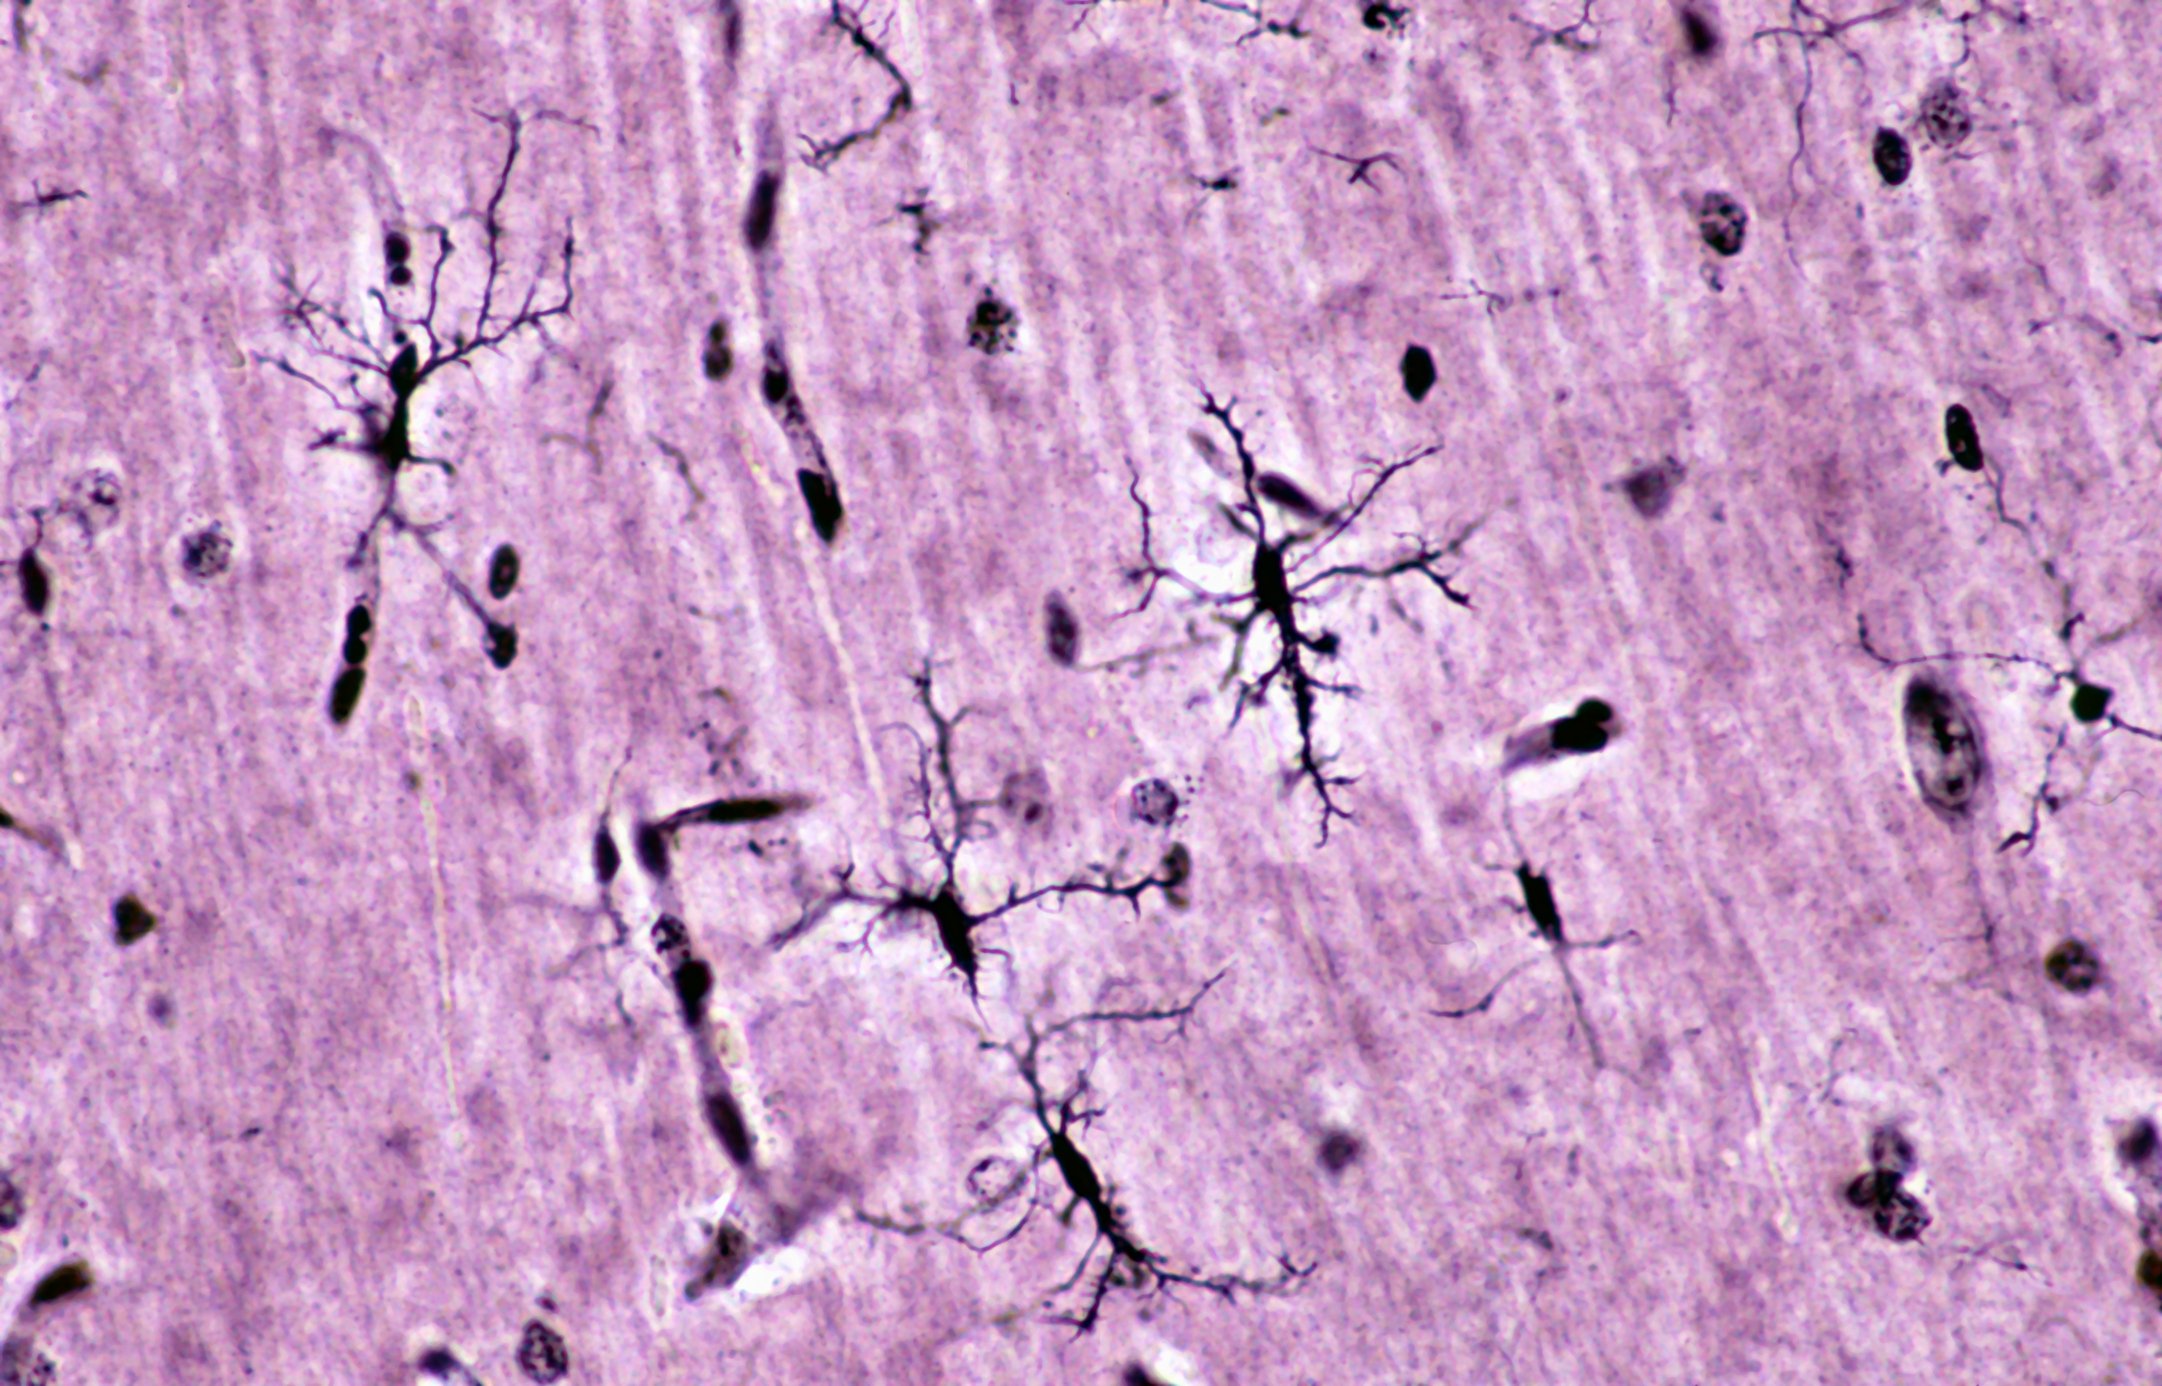

Entre 0,3% e 1% dos pacientes com neuroborreliose sofrem de eventos cerebrovasculares. Estes manifestam-se principalmente como insultos isquémicos. Os pacientes com uma manifestação cerebrovascular de neuroborreliose têm geralmente uma fase prodrómica com sintomas não específicos semanas ou meses antes do primeiro evento vascular. A razão aguda mais frequente para a hospitalização, com até 76%, é um AVC isquémico. Característica é a ocorrência de vários eventos apoplectiformes no curso. Em quase todos os doentes, há uma combinação de aumento da contagem de células linfocitárias e proteínas muito elevadas no LCR. De acordo com as directrizes, recomenda-se o tratamento antibiótico precoce com ceftriaxona ou doxiciclina durante duas a três semanas. Além disso, a terapia adjuvante com ASA trombo e cortisona pode ser considerada. A contagem de células no LCR permanece geralmente elevada durante muito tempo, apesar de uma resposta à terapia. Globalmente, insultos isquémicos agudos e alterações de ressonância magnética em múltiplas áreas do estroma em áreas endémicas devem ser considerados como uma manifestação cerebrovascular da neuroborreliose e devem ser realizados esclarecimentos adicionais por punção lombar. Uma fase prodromal com sintomas não específicos, tais como cefaleia ou fadiga durante meses é característica. A presença adicional de aneurismas intracranianos é uma indicação adicional de uma manifestação rara de neuroborreliose. Em caso de suspeita, a antibioticoterapia também deve ser iniciada.